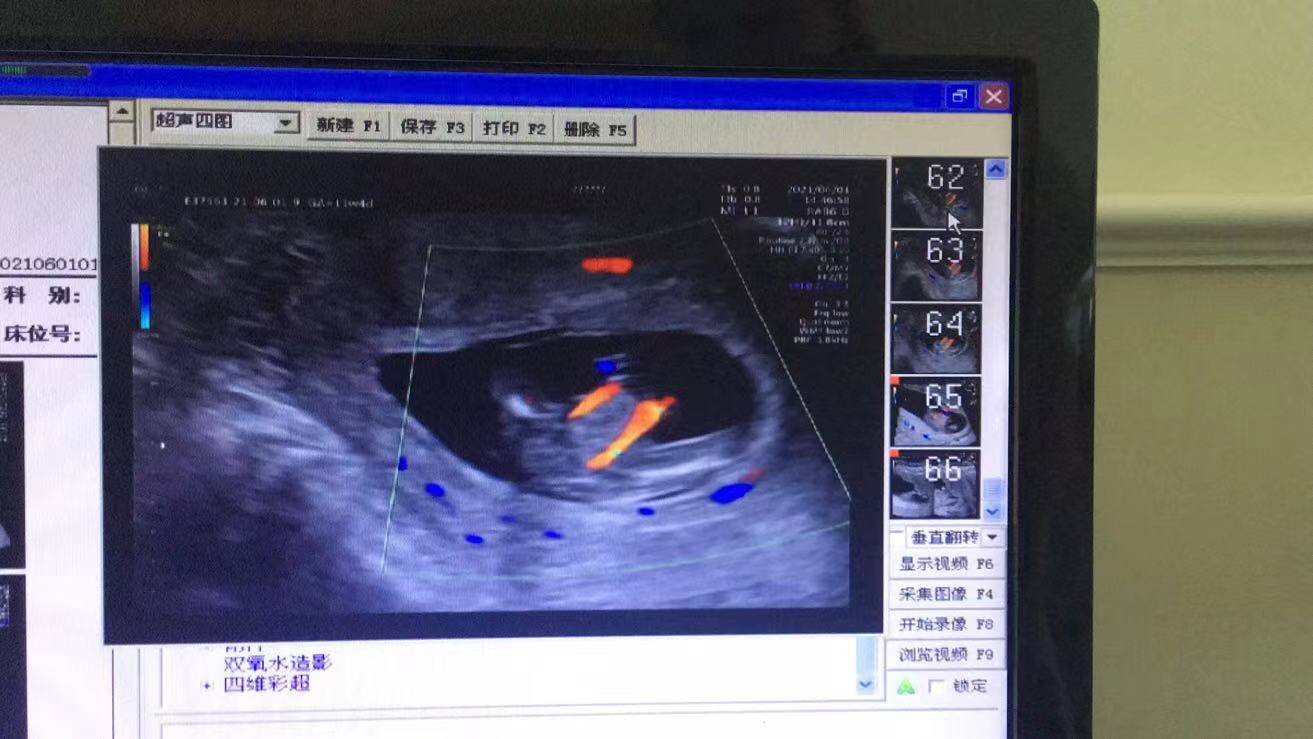

原來,前幾天,懷孕11周的她來到武漢仁愛醫(yī)院超聲科做了NT(頸項(xiàng)透明層)檢查,發(fā)現(xiàn)腹中胎兒有些異樣,寶寶的右腳缺失,脊柱部也有異常,超聲科醫(yī)生立刻叫來了超聲科王娟主任進(jìn)行再次檢查,經(jīng)過30分鐘的仔細(xì)探查后,王主任終于看清楚了胎兒的情況,并最終確診:“腹中胎兒右小腿長(zhǎng)骨發(fā)育不良,右腳缺失,脊柱腰骶段排列異常,會(huì)陰部包塊,考慮泄殖腔外翻可能。”王娟介紹。

(王女士NT檢查結(jié)果)